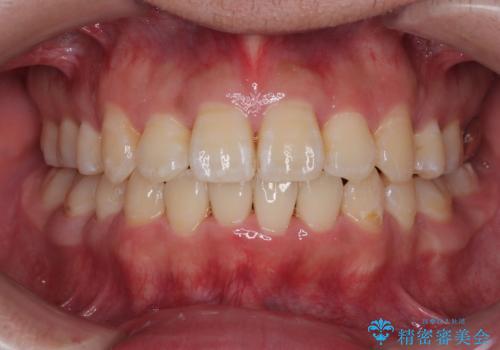

- 「歯並び全体のデコボコをきれいに整えたい」とのご希望で、20代男性の患者様が来院されました。

特に前歯部の叢生(歯の重なり)が強く、見た目だけでなく歯磨きのしにくさも気にされていました。

診査の結果、上下前歯に強い叢生が認められ、歯をきれいに並べるためのスペースが明らかに不足していました。